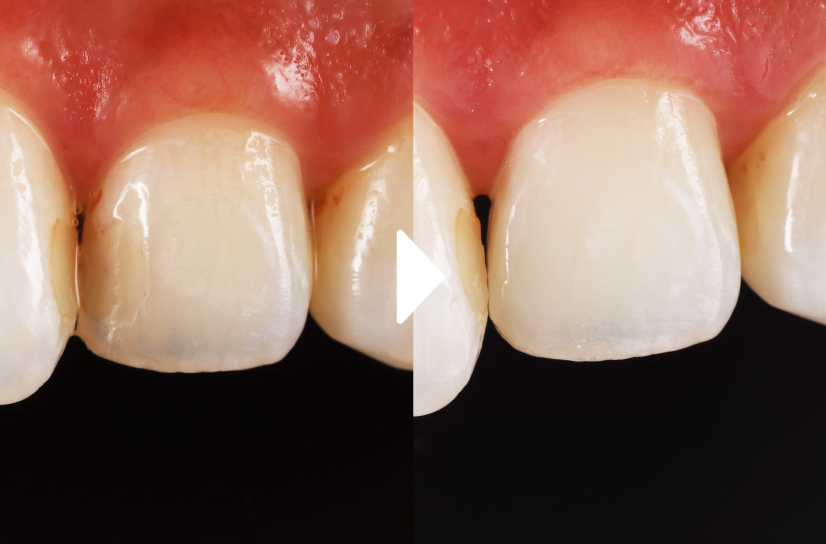

前歯の審美修復治療

左上2にむし歯がありコンポジットレジン(CR)を使って修復しています。むし歯の範囲によっては歯を削る量を最小限にし審美的に修復することが可能になります。